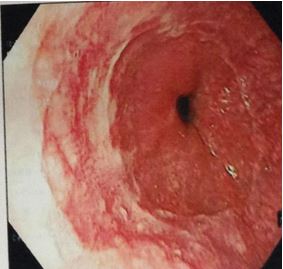

Nội soi dạ dày:

- Niêm mạc hang vị xung huyết kèm một số trợt nông, trợt lồi, mặt trước hang vị có ổ loét nông kích thước 1,2 cm

Hình 1:Hình ảnh nội soi dạ dày(vòng tròn đỏ là tổn thương)